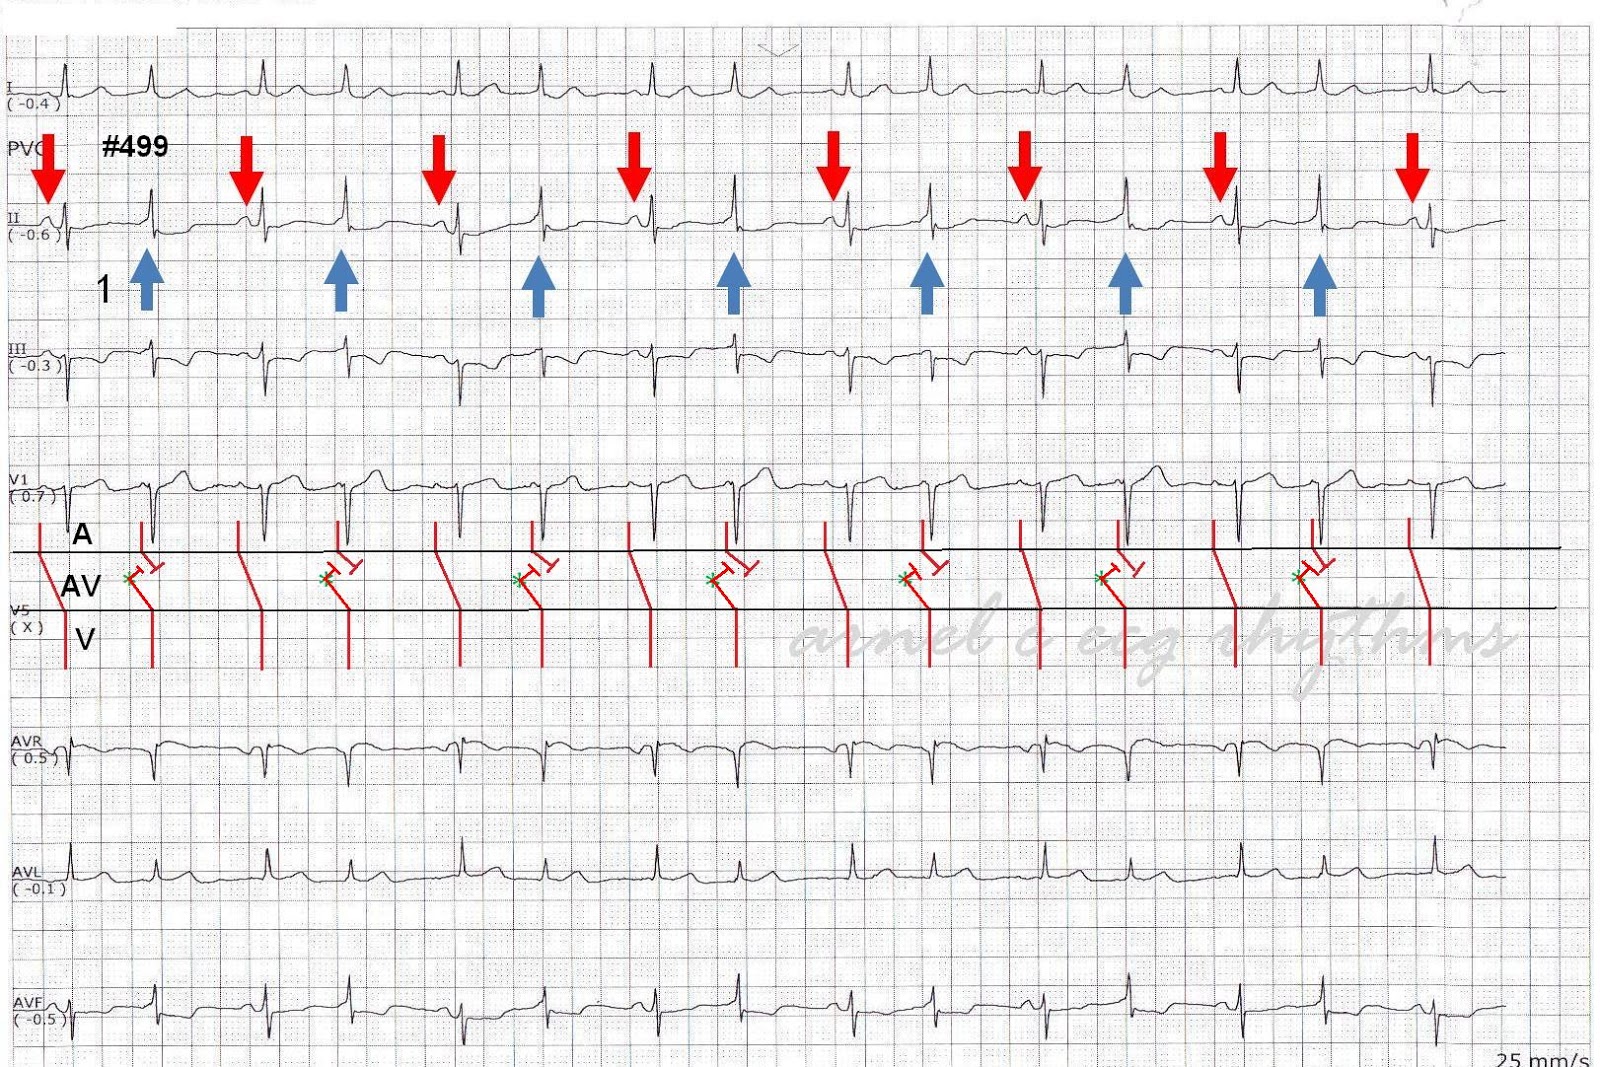

ECG Rhythms Isorhythmic AV dissociation

ECG Rhythms Isorhythmic AV dissociation What Is Av Dissociation This term indicates only the occurrence of independent atrial and ventricular contractions and may be caused by entities other than complete heart block (e.g. Atrioventricular (av) dissociation is a condition in which the atria and ventricles do not activate in a synchronous fashion but beat. Atrioventricular (av) dissociation is a condition in which the atria and ventricles do not activate. What Is Av Dissociation.